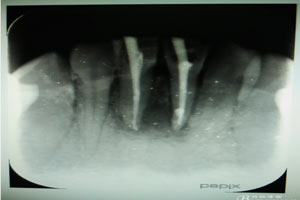

圖18.術(shù)后的根尖片影像檢查:

術(shù)后局部冷敷一日,靜脈滴注抗生素三日。同時(shí)注意口腔衛(wèi)生。